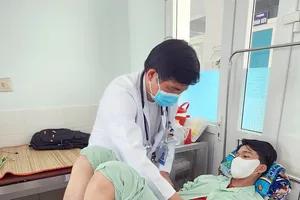

Trước đó 20 ngày, người nhà phát hiện chị của cháu N.T đưa tay vào miệng cháu để cố lấy ra vật gì đó không rõ. Sau đó cháu H.T ho sặc sụa, trong miệng có ít máu chảy ra và được đưa đi khám bệnh, điều trị trong nhiều ngày nhưng tình trạng ngày càng nặng hơn.

Bệnh nhi được chuyển khám tại BV tỉnh và phát hiện có cây đinh trong phổi nên tiếp tục chuyển lên BV Nhi đồng 1 TPHCM để lấy cây đinh ra.